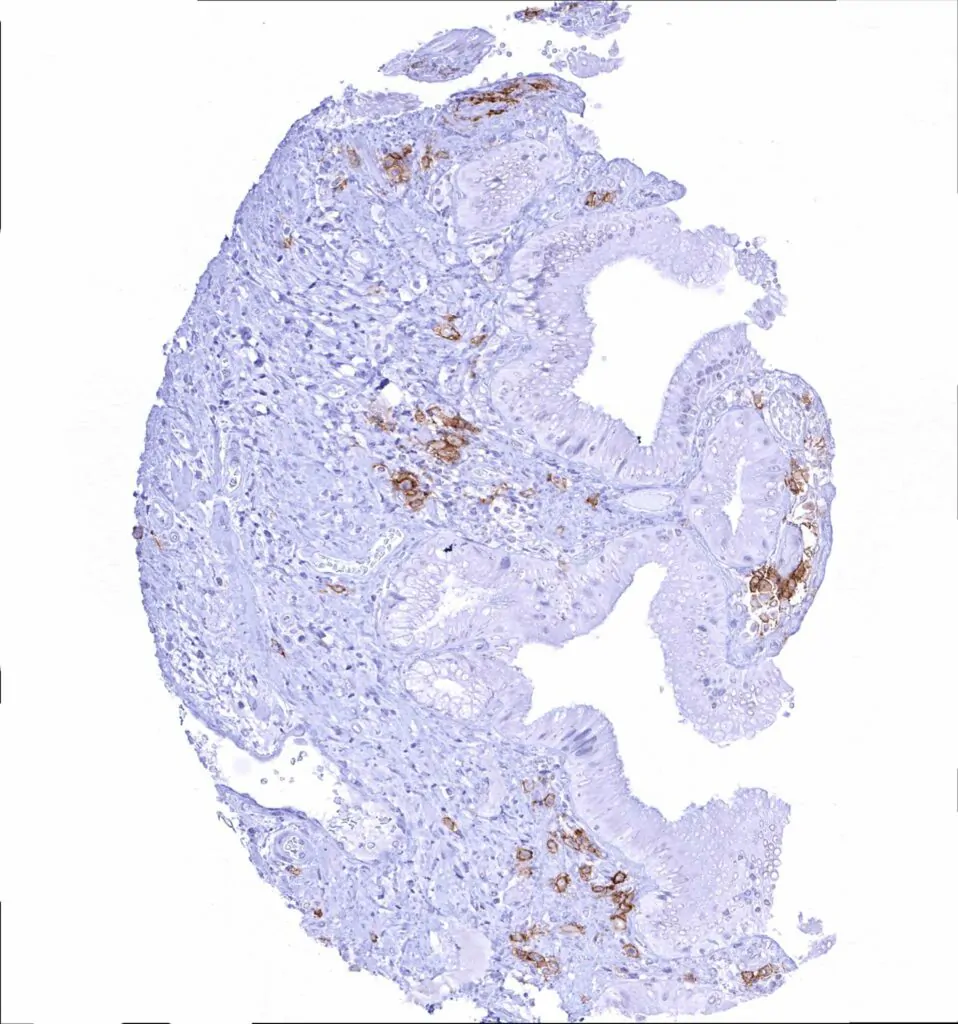

Appendix, mucosa – Strong CD38 staining of a subset of inflammatory cells

Appendix, mucosa